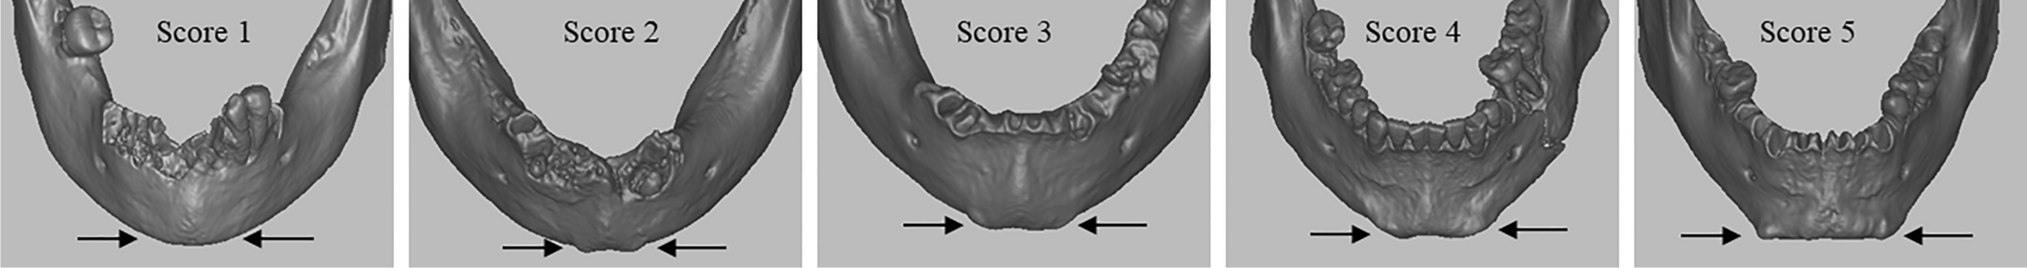

The method by Walker (2008) encompasses five traits (nuchal crest, mastoid process, supra-orbital margin, glabella, and mental eminence), scored according to an ordinal scale from 1 (female/gracile) to 5 (male/robust), with scores 2 and 4 corresponding to "probably female" and "probably male" morphologies, respectively, and score 3 to "indeterminate". We based our scoring on the criteria listed by Walker (2008) and MorphoPASSE [5]. Considering the finding by Braun et al. (2022), we will divide the mental eminence trait into the mental tubercles and the sagittal mental protuberance in our study, in addition to scoring the traditional mental eminence. With this attempt, we keep two features apart that make the human menton 'much more complex' in its expression [49] than the description in Walker [4] might suggest. To score the expression of the mental tubercles and the mental protuberance, we applied the same scoring protocol (scores 1 to 5), with minimal and maximal expression of the traits corresponding to score 1 and score 5, respectively (Figs. 1 and 2, Table 2).

Fig. 1

CT scans of mental tubercles (black arrows) scores 1 to 5 with increasing expression of the trait, independent from mental protuberance. Individuals Ins Kirchgemeindehaus (3465, 3466, 3469) and Twann (3365 and 3371), respectively

Fig. 2

CT scans of mental protuberance (white arrows) scores 1 to 5 with increasing expression of the trait, independent from mental tubercles. Individuals Ins Kirchgemeindehaus (3543, 3472, 3469, 3529) and Steffisburg (3975), respectively